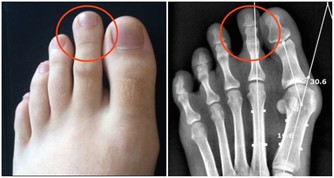

1.異常腫塊:身體任何部位發現腫塊,並有逐漸增大的現象,應引起重視。如淋巴瘤可出現淋巴結的腫大。